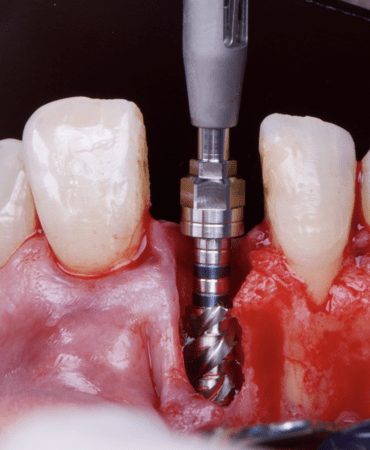

The surgical protocol began with the atraumatic extraction of tooth 1.1 to preserve as much of the alveolar socket as possible. Immediately following extraction, an N1 implant was placed into the socket using a guided surgical approach to ensure ideal three-dimensional positioning. The “one abutment one time” technique was applied to minimize soft tissue manipulation during the healing phase, which is particularly important in esthetic areas.